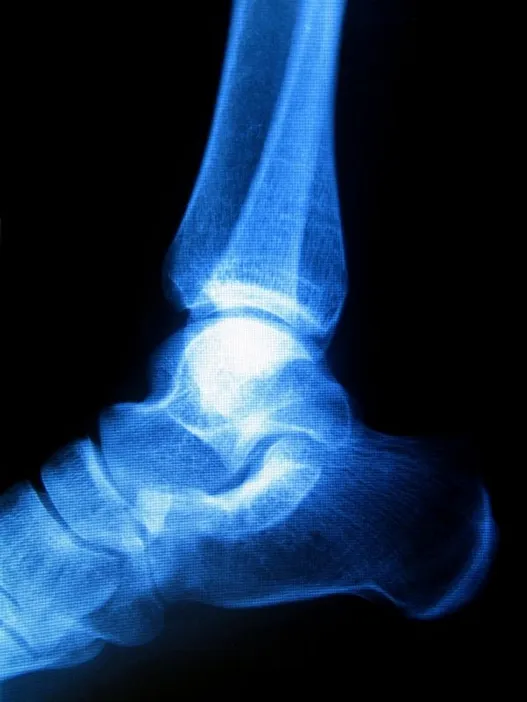

Sometimes known as “pump bump” because of its prevalence among women who wear pump-style shoes, Haglund's deformity can occur in one or both of the feet. If you are suffering from Haglund's deformity, you will most likely have noticed a bony enlargement at the back of the heel. This inflammation is caused when the bursa, a fluid­-filled sac between the Achilles tendon and your heel bone, becomes irritated. Other signs of Haglund's deformity include pain where the Achilles tendon and the heel meet, swelling, and redness.

While genetic factors influence your likelihood to develop Haglund’s deformity (high arches, a tight Achilles tendon), stiff shoes are also a major risk factor.